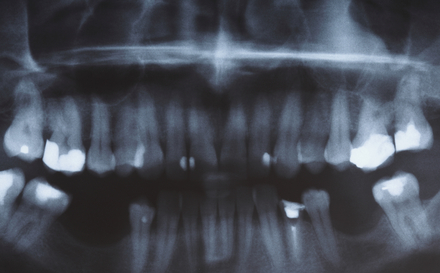

What Do My Dental Records Look Like?

What Do My Dental Records Look Like? Your dental records are a combination of different types of information. There are written descriptive records, photographic records and charts. The descriptive records are much like what you see your GP typing up when you have an appointment with your doctor. They are readable and understandable to most…